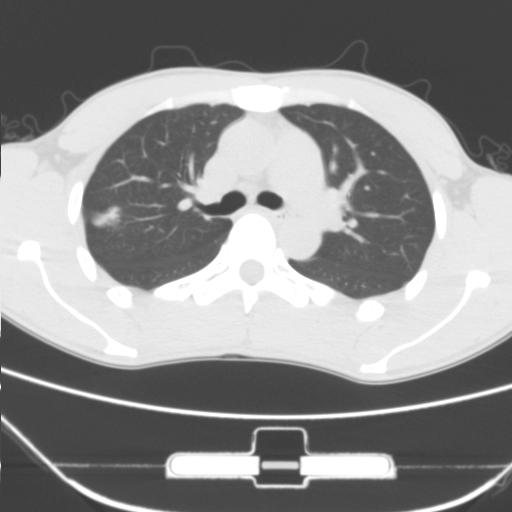

车祸伤者

右肺上叶后段近胸膜下结节样异常密度灶,似见分页及毛刺,考虑右肺上叶周围型肺ca,建议穿刺病理检查

周围型肺ca与炎性假瘤待鉴别。建议穿刺病理检查

考虑周围型肺癌

考虑周围型肺癌可能性大,建议穿刺病理检查

缺乏病史,症状体征,但这个孤立结节具备了几乎所有的恶性征象:分叶,毛刺,空泡征,胸膜凹陷征,血管集束。

考虑右肺上叶后段周围型肺癌。